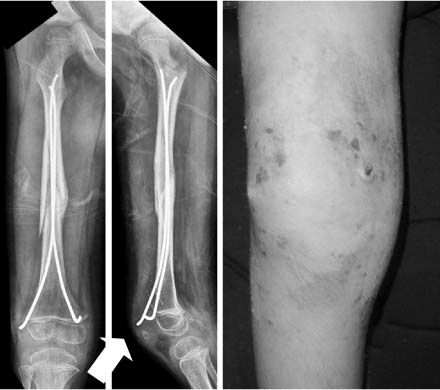

Fig. 2

When flexible nails are remained too long distally, they will protrude the skin and soft tissue (arrow) and it provokes the infection and knee stiffness.

Fig. 3

Although the femoral fracture was well reduced by flexible nails (left), the nails were bent and varus deformity occurred because the patient had a weight-bearing too early (right).